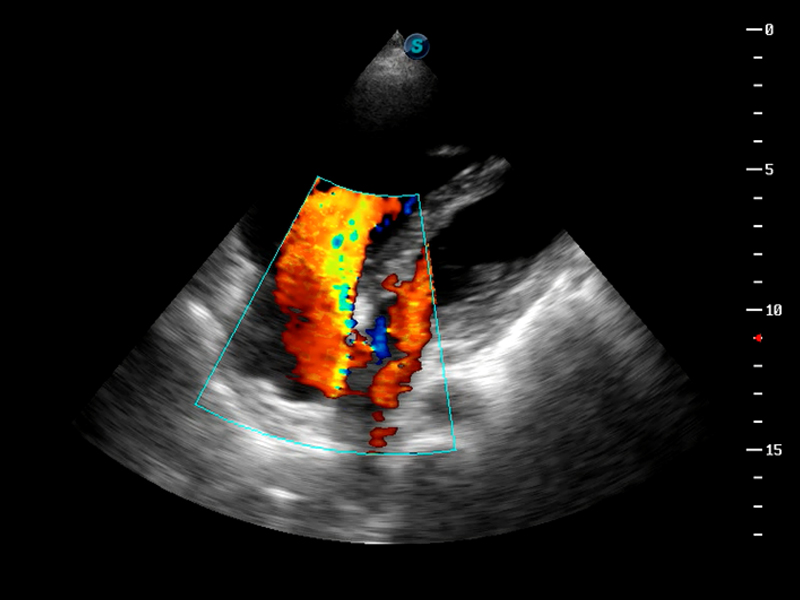

S9

S9便携式彩色多普勒超声诊断仪是环球UG官网研发的高端便携彩超设备,外观设计新颖、产品性能卓越。S9在便携超声领域采用了突破传统的触摸屏交互设计,并以先进的软件硬件技术和设计理念,为您带来清晰的图像质量、稳定的工作性能和便捷的操作体验。

AutoC智能血流追踪